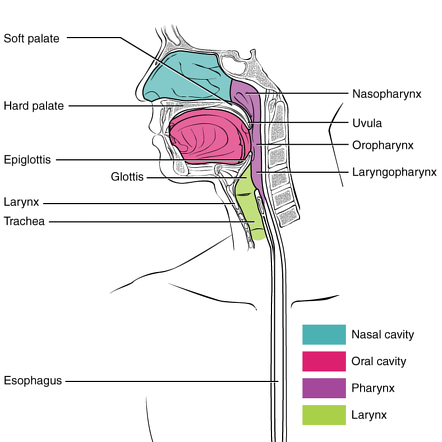

what are the divisions of the pharynx

regions of the pharynx

nasopharynx

oropharynx

laryngopharynx

important point about the divisions of the pharynx

divisions of the pharynx are only descriptive

not demarcated by physical borders, only anatomical landmarks

nasopharynx: borders

nasopharynx

extends from behind the nose/ nasal cavities

to the soft palate

nasopharynx: which tract is it a part of

the nasopharynx is a functional part of the respiratory tract

nasopharynx: what structures does it contain

pharyngeal tonsils/ adenoids

opening of auditory tubes (Eustachian)

the tubal tonsils

oropharynx: borders

oropharynx

from below the soft palate

to the tip of the epiglottis

laryngopharynx: borders

laryngopharynx

from the tip of the epiglottis

to the lower border of the cricoid cartilage